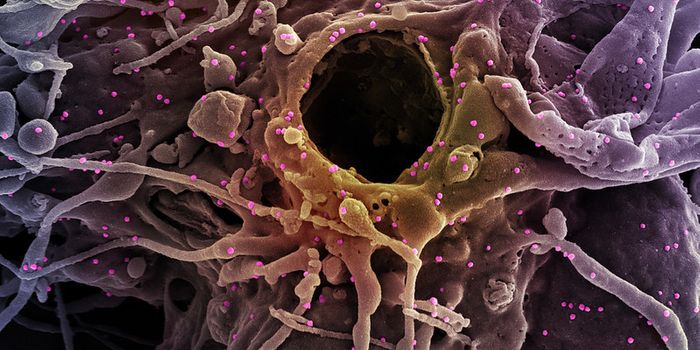

AUG 26, 2024Clinical & Molecular DXA colorized scanning electron micrograph depicts a Kupffer cell. / Credit: Thomas Deerinck, National Center for Microsco ...